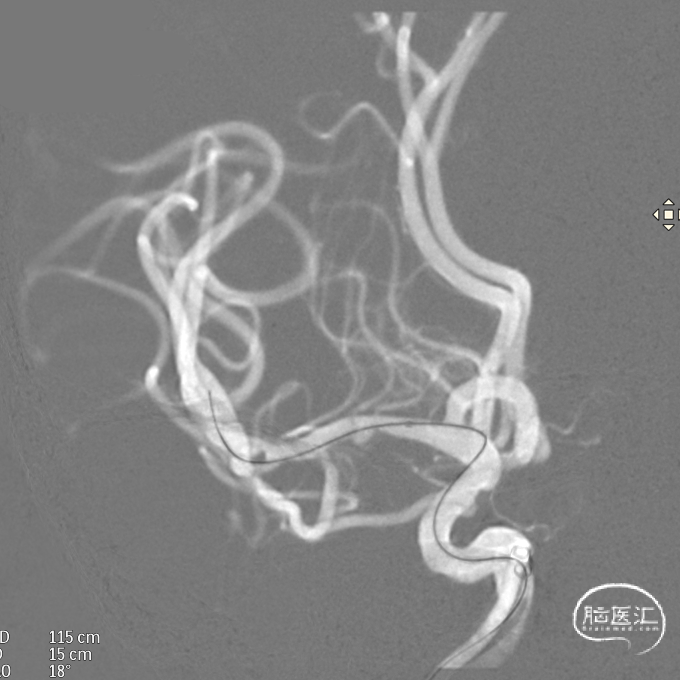

微导管到位:Synchro微导丝引领支架微导管通过病变血管进入大脑中动脉M1段远端。

支架到位,远端打开(正侧位):4.75-20mm支架在大脑中动脉M1段打开,回撤至C6段远端锚定。支架释放过程中,轻柔推送支架系统,可见支架导管沿血管壁大弯侧走行,支架打开良好。

支架中段打开: